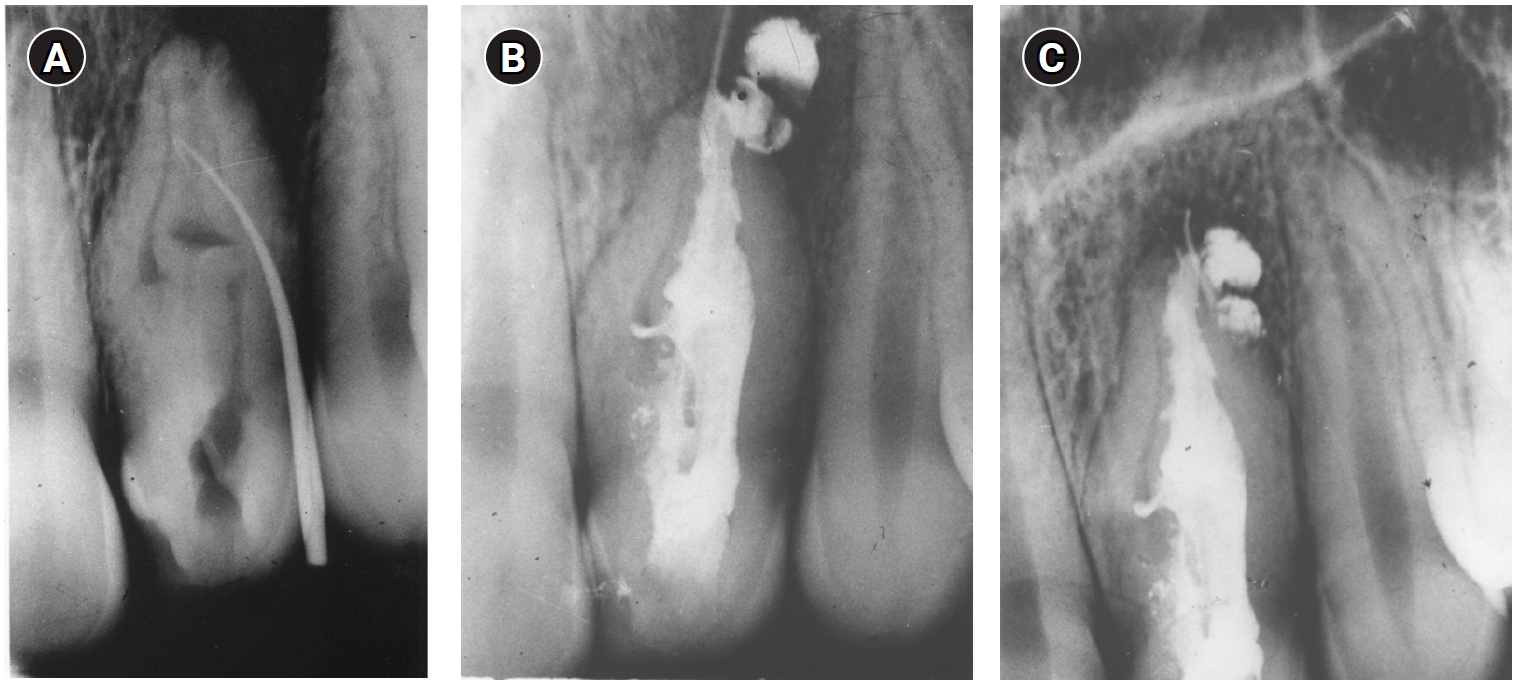

In 2021, when the patient (now aged 63 years) was referred by the treating dentist for evaluation, the tooth was still clinically asymptomatic with normal periapical tissues (Figure 4). The patient did not attend any follow-up appointments after 2021, despite multiple attempts to contact and recall her. A summary of events and outcomes is presented in Table 1.

Figure 4.

Figure 4. Radiograph taken in 2021 of tooth #22 showing normal periapical tissues, 10 years after endodontic reoperation.